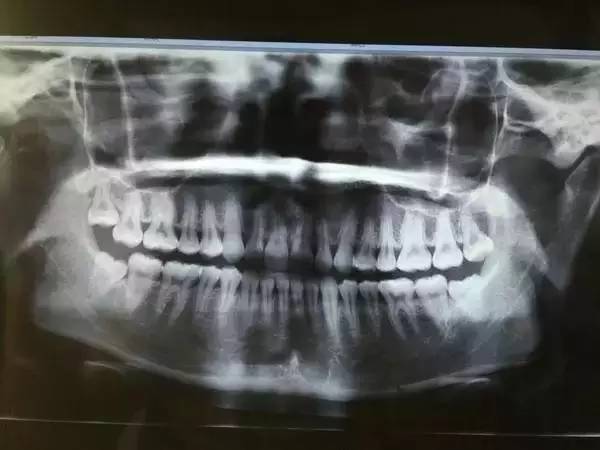

一般患者不自知,而由牙醫(yī)以X光確診得知。一般智齒萌生的空間缺乏,而會倒在第二大臼齒上,因而形成第二大臼齒清洗不易,乃至是牙齒部分吸收的表象,形成患者不舒服或牙疼。

640 (22).jpg